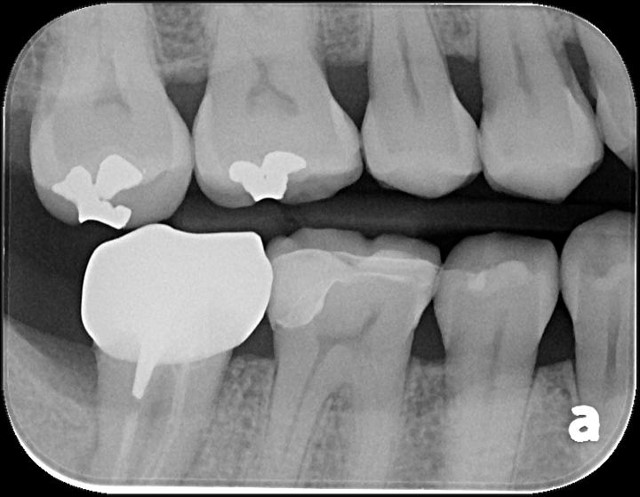

冠塊體體製備

當蛀牙破壞程度大

陶瓷冠塊體是根據蛀牙的窩洞量身訂做,不管是顏色、精密度都是最佳的選擇,因此是非常美觀與持久的填補窩洞材料與技術